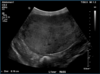

What is shown in these images?

A

generalized hepatomegaly:

-pendulous abdomen with no fluid accumulation

-likely hyperadrenocorticism/cushing’s